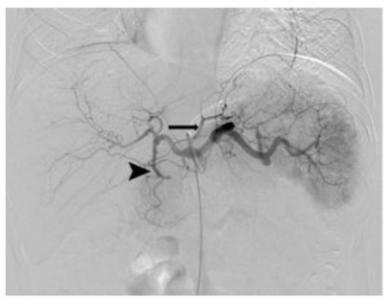

L’embolisation bariatrique permet la perte de poids, mais comment ? L’embolisation gastrique ou bariatrique, une procédure moins invasive, qui consiste à injecter des billes microscopiques sous contrôle d'imagerie dans l'artère alimentant l’estomac en sang. Les perles bloquent le flux sanguin et réduisent la production de ghréline, l’hormone qui stimule la faim. De premières études montré l’efficacité de l’embolisation pour la perte de poids, mais, comme le souligne ici l’auteur principal, le Dr Edwin A. Takahashi, radiologue vasculaire à la Mayo Clinic : « Il n’existe aucune donnée sur ce qui contribue à la perte de poids, que les patients perdent ou non de la graisse, ou encore de la masse musculaire, ou enfin une combinaison des deux ».